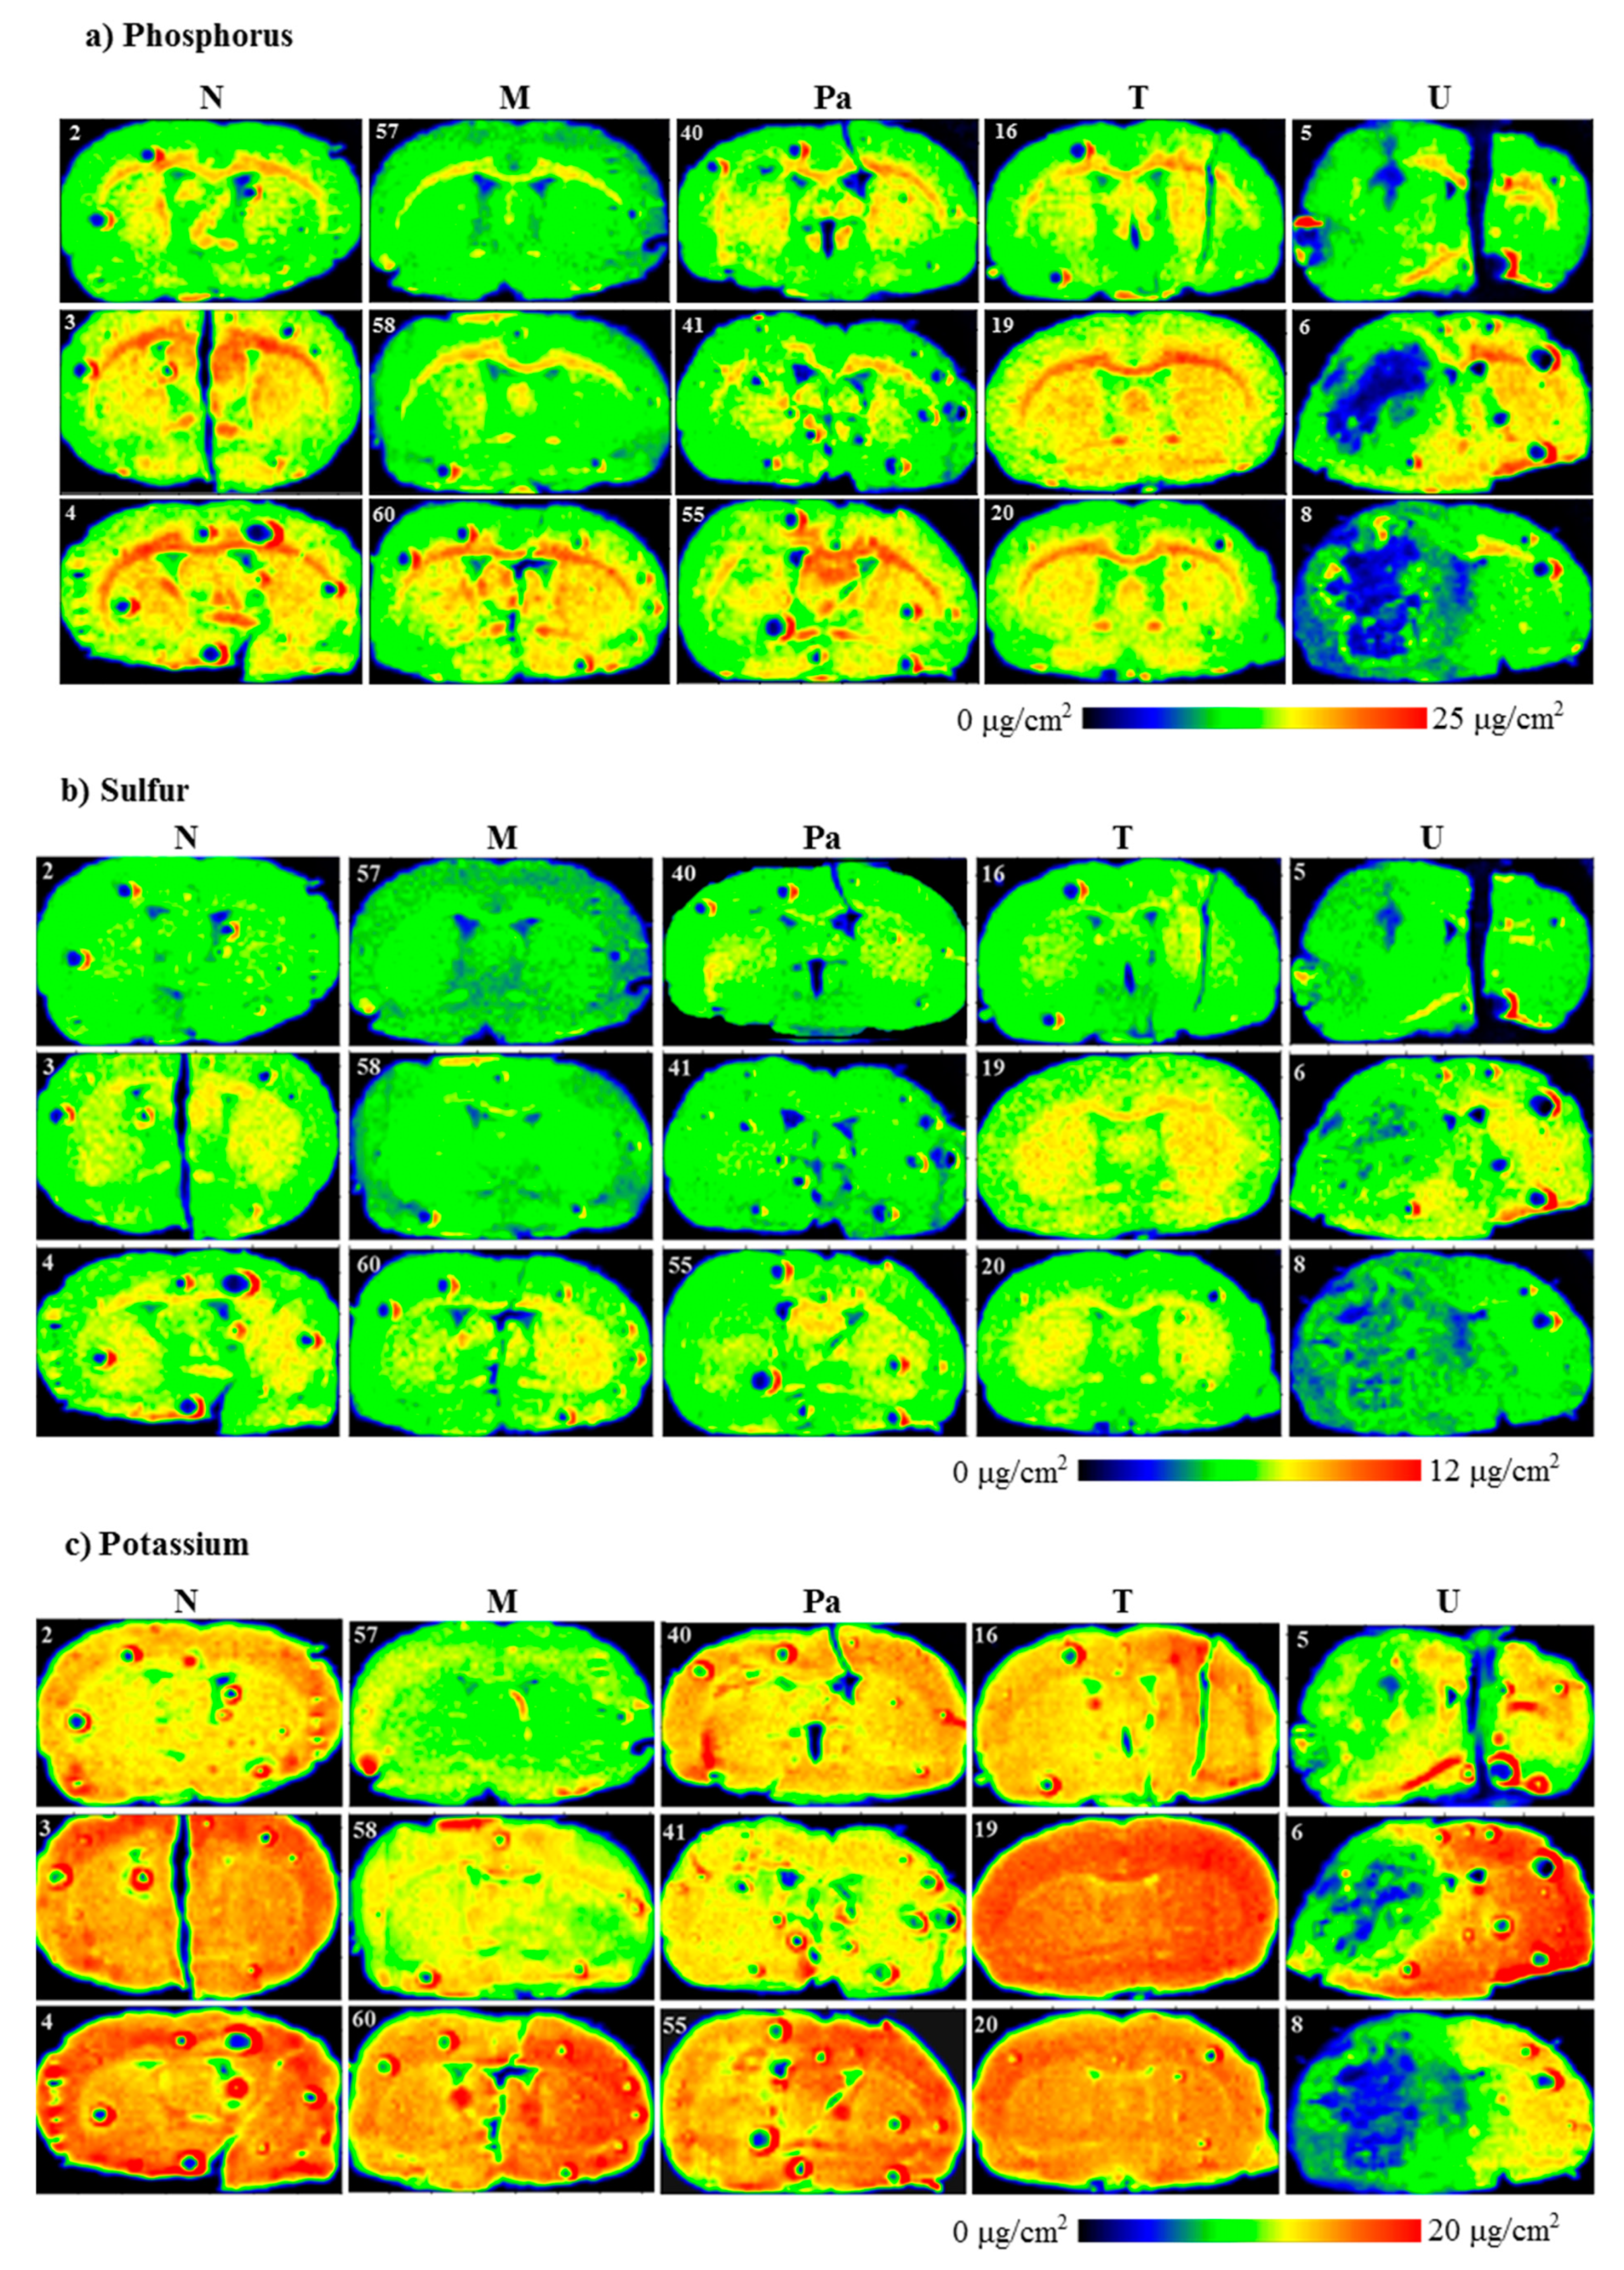

Evaluating the distributions of the elements under interest (P, S, K, Ca, Fe, Cu, Zn and Se) in the scanned brain slices was the first step of our investigation. The results of the topographic elemental analysis for the representative samples that originated from all the experimental groups are provided in Figure 3.

Figure 3.

Topographic elemental maps of brain slices taken from the rats of all experimental groups for: (a) phosphorus, (b) sulfur, (c) potassium, (d) calcium, (e) iron, (f) copper, (g) zinc and (h) selenium. Color scales express areal densities of elements in μg/cm2. In the case of Ca, large differences in areal densities were observed between groups N, M, Pa, T and group U. Two different scales were applied for better visualization of the distribution of this element.

As one can see from Figure 3a, a clear decrease in P accumulation in the implanted brain hemisphere and especially in the area of tumor development was found for the rats from the U group. A reduced element content was noted compared to the naive hemisphere within the same sample, as well as compared to the left hemisphere of the normal animals. A similar relation was observed for the animals implanted with patient-derived glioma cells. Additionally, for them, the area of the tumor determined from microscopic examinations corresponded with the region of a slight decrease in phosphorus accumulation. In the case of groups M and T, we did not observe any changes in P distribution in the regions of interest.

Topographic analysis of the maps of S distribution (Figure 3b) illustrated changes in the accumulation of this element in the left hemispheres of the animals implanted with the U87mg cells. For this group of rats, the areas of the reduced S content, compared to the intact hemisphere as well as to the left hemispheres taken from the control rats, were observed. These differences were not found in the case of the remaining experimental groups. A similar observation was made in the case of K distributions. The clear decrease in its accumulation occurred only in the areas corresponding to the tumors developed in the brains of the animals from the U group.

Ca and Fe are two elements, the distribution of which was disturbed both within the place where the glioma cells were implanted and culture medium was administered. The accumulation of both elements increased in the regions of DMEM administration and T98g cells injection (M and T groups, respectively), as well as the tumor development in the case of the Pa and U groups.

The topographic maps recorded for Ca and Fe showed a great heterogeneity of element accumulation in the tumor bulk developed from U87mg cells. A significant increase in Ca content was found in the inner area of the tumor, while Fe accumulated more in its border layers. Furthermore, regions of an elevated accumulation of Ca and Fe corresponded with the tumor areas presenting a different morphological structure, which can be seen in Figure 2, illustrating microscopic images of the scanned tissue sections.

The results obtained for Cu showed a substantially elevated areal density of this element in the tissue directly adjacent to the tumor developed from the U87mg cells. Additionally, in the case of the U group, the distribution of Cu within the tumor was heterogeneous and its level was lower in the external layer than the inner region. In turn, the level of Cu was generally lower in the tumor compared to its surroundings for the samples taken from the animals belonging to the Pa group.

Zn accumulation showed anomalies in the samples taken from the animals representing the Pa and U groups. A decrease in this element content was recorded in the area of the tumor developed from the U87mg cells. Furthermore, the reduced Zn level occurred mainly in the inner part of the tumor and was usually correlated with the area of lower P accumulation. The tumor developed from patient-derived cells presented the heterogeneous Zn distribution with a slightly elevated content compared to the surroundings.

In the examined tissue slices, Se was selectively accumulated in the tumors developed in the animals from the Pa and U groups. Moreover, its distribution within the tumor bulk was generally homogenous and corresponded with the area of the tumor determined based on microscopic images.